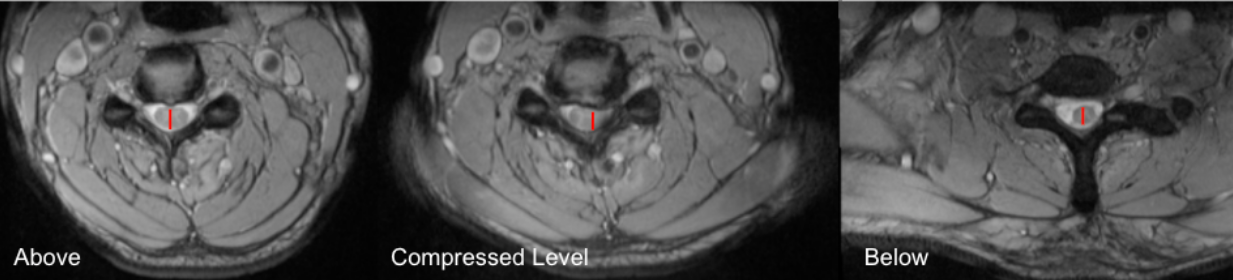

Maximum Spinal Cord Compression (MSCC) is a quantitative MRI-based metric that expresses the percentage reduction in spinal cord diameter at the site of maximal compression relative to the patient’s own normal cord diameter.

By normalizing the compressed diameter to the average of adjacent, non-compressed segments, MSCC accounts for inter-patient variability in cord size and provides a robust, patient-specific estimate of compression severity. MSCC is widely used in the evaluation of degenerative cervical myelopathy, disc–osteophyte complexes, OPLL, trauma, and other compressive myelopathies, and correlates with neurologic deficit severity and outcomes.

•  Select axial T2-weighted MRI slices at three levels:

• Above the lesion (normal cord)

• At the level of maximal compression

• Below the lesion (normal cord)

•  Measure Dᵢ (minimum diameter at lesion):

• At the compressed level, measure the shortest anteroposterior (AP) diameter of the spinal cord.

• Measure normal cord diameters:

• Measure the AP diameter of the cord at one normal level above and one normal level below the lesion.